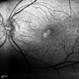

- Stephan Morrow, Midwest Eye Institute Indianapolis Indiana

Scanning laser ophthalmoscope

Heidelberg Spectralis - Description

- 8-year-old male, flourescein angiogram, late phrase 4:22 minutes, OD.